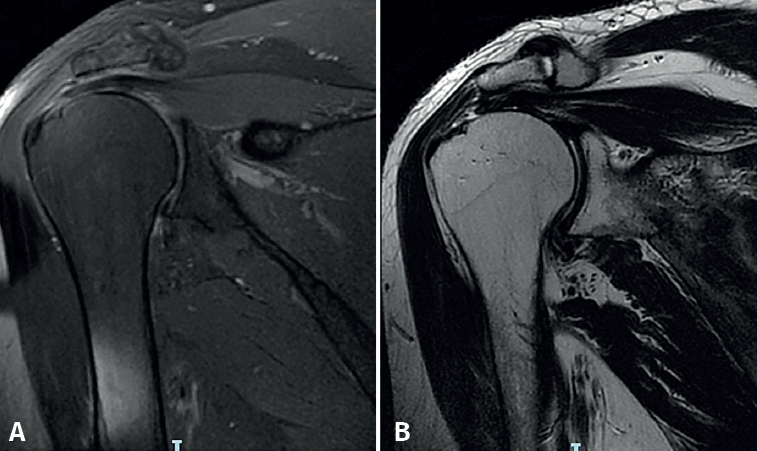

The magnetic resonance imaging (MRI) study prior to surgery allows us to assess the percentage of rupture according to the degrees of tendon retraction established in the Patte classification (Figure 1).